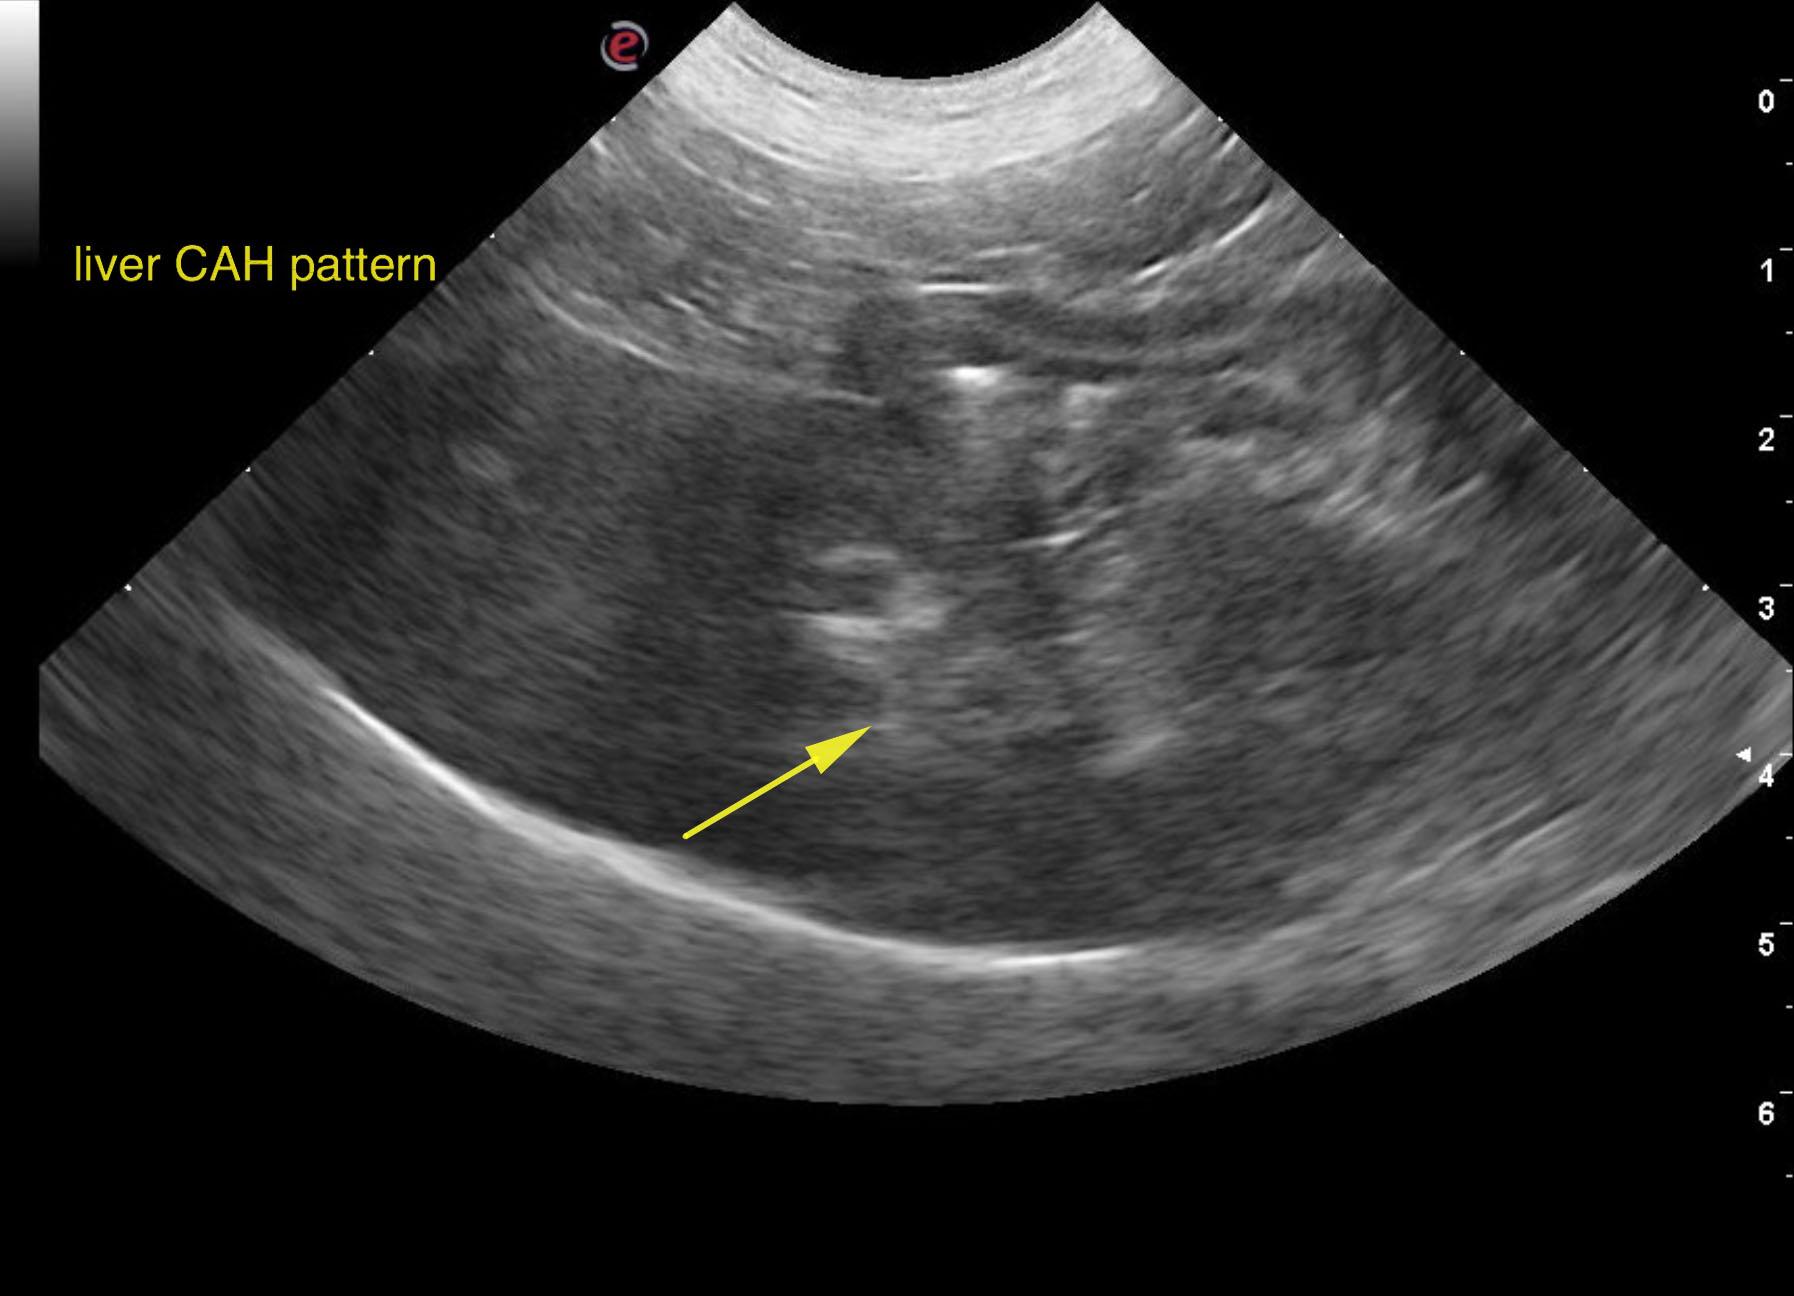

A 7-year-old female Beagle with a history of reduced appetite for a few days was presented for evaluation vomiting and hemorrhagic diarrhea. On physical examination, icterus was present. Urinalysis showed specific gravity of 1.004, bilirubinuria, and hematuria. Abnormalities on serum biochemistry were severely elevated ALT (1247) and ALP (1057) activity and bilirubin (11.9) and low BUN. CBC and radiographs were both within normal limits.